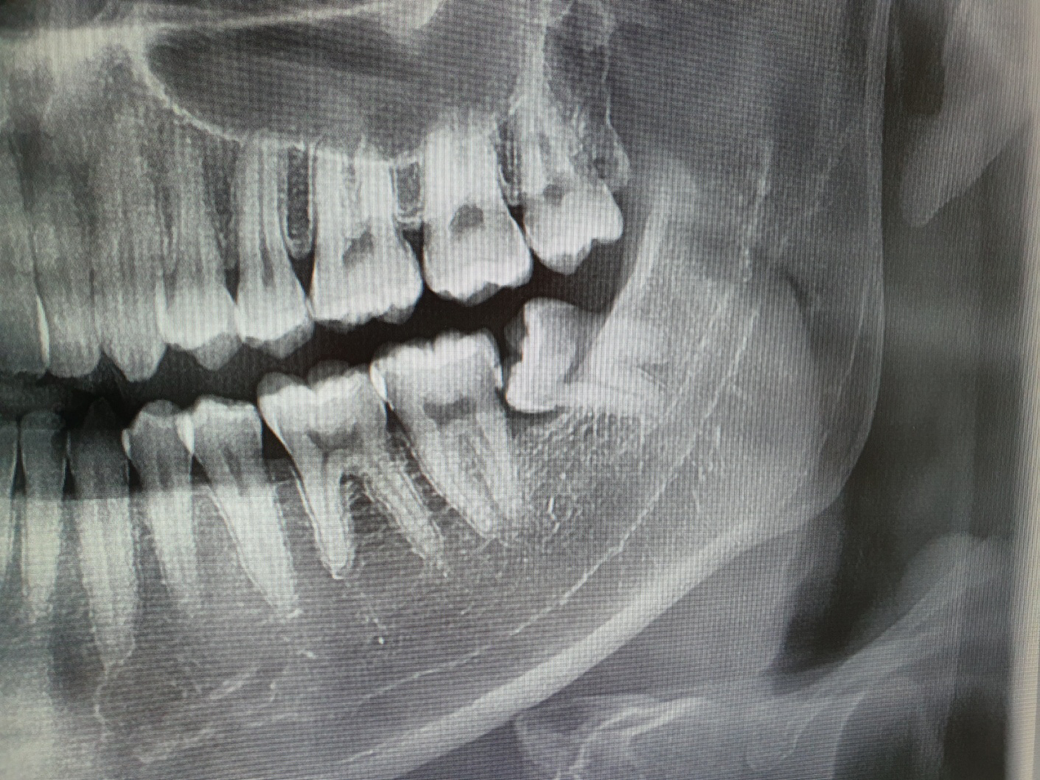

치아 사진과 CT를 보시고 치료가 필요한지 확인 해 주실 수 있으실까요?

아래 사진은 제가 직접 찍은 사진입니다.

치과에서 검사를 받아보니, 치아가 착색된 것 같다고 하시며 딱히 치료하지 않고 좀 더 지켜봐도 좋다고 하시더라구요.

만약 썩었다면 CT 상에 검은색으로 보여져야 한다고 하시더라구요.

누워있는 사랑니 부분입니다.

방사선 사진은 CT가 아니고 파노라마 사진입니다. 사진상으로 보면 착색은 아닌거 같습니다. 그리고 충치여부를 확인하기 위해서는 파노라마 사진보다는 작은 사진을 찍어봐야 제대로 알수 잇을것같습니다.

파노라마 사진을 봤을 경우에는 충치가 있어 보이진 않습니다.

하지만 하악의 사랑니는 앞에 있는 치아에 충치를 유발 할 수 있기 때문에 발치를 해 주는 것이 더 좋을 것으로 생각 됩니다.

해당사진은 파노라마 방사선 사진인데 방사선 사진상에서는 뚜렷이 보이지는 않지만 육안으로 봤을 때는 사랑니 교합면(윗면)과 옆면에 걸쳐 충치가 있는 것으로 판단됩니다.

다만 여기서 부분매복 사랑니는 충치가 있으면 빼면 되지만 지금 더 중요한 문제는 사랑니가 옆의 두번째 어금니에도 영향을 줄 수 있다는 점입니다. 원래 부분매복 사랑니는 문제를 일으킬 소지가 다소 있긴합니다

예방적으로 뽑아주는 것도 나쁘지 않을 것 같습니다